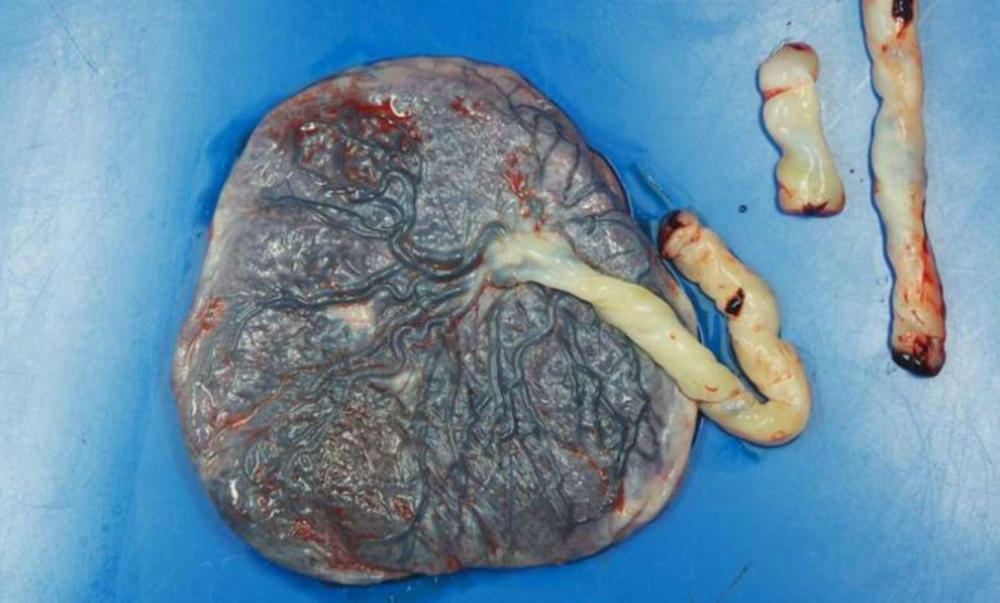

Korona virus po svoj prilici, kako tvrde naučnici, oštećuje posteljice trudnica i smanjuje dotok krvi bebama u stomaku.

To su rezultati nedavno sprovedenog malog istraživanja u kome su naučnici pregledali posteljice 16 majki i na svakoj od njih pronašli vidljivo oštećenje. Lezije i ugrušci krvi su pronađeni u posteljicama, koje su ključni element za obezbeđivanje dotoka kiseonika i nutrijenata za fetus.

Problemi sa dotokom krvi u posteljicu mogu da dovedu do pothranjenosti novorođenčeta, oštećivanja njegovih organa, pa čak i smrti. Međutum, dobra vest je da nijedna od beba majki koje su učestvovale u ovom istraživanju nisu imale zdravstvene probleme. Ipak, naučnici koji su sproveli eksperiment kažu da ih rezultati brinu i da ovo istraživanje pokazuje da lekari treba da posvete dodatnu, veliku pažnju trudnicama u toku pandemije.